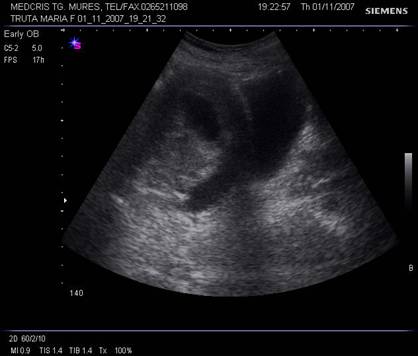

Fig. nr .348.Uter postmenarcha ,la ecografia abdominala , sectiunea sagitala